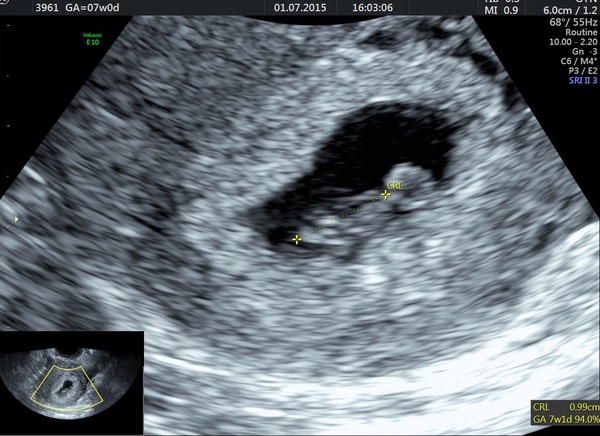

Another good scan! Saw its little heart flickering away and heard it beat. Over the moon :)

Yay congrats Abfab! Have clearly completely lost the plot and forgotten who's getting scanned when, shall claim baby brain. Lovely pic Smile

BUT had a lovely scan yesterday morning and found out we're a bit further along than we thought with a little heart beating away Smile so it really does vary x